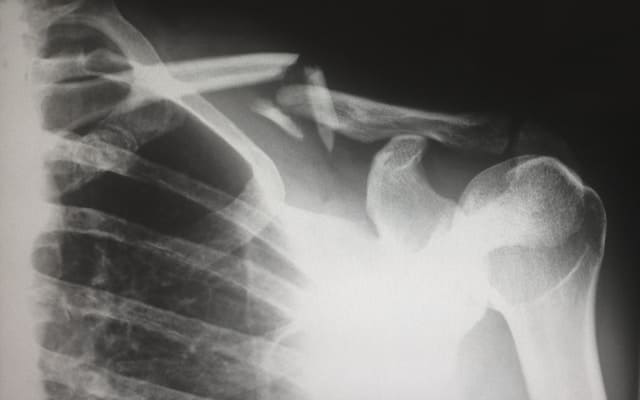

예전에는 넘어져도 금세 털고 일어났던 일이 이제는 조심스러워지고, 허리나 무릎이 쉽게 뻐근해지며 오래 서 있거나 앉아 있다가 일어날 때 몸이 굳은 듯한 느낌을 받는다. 이러한 변화는 관절의 문제만이 아니라, 뼈의 밀도와 구조가 서서히 변하고 있다는 신호일 수 있다. 60대 이후에는 뼈를 만드는 속도보다 소모되는 속도가 점점 빨라진다. 젊을 때는 뼈가 자연스럽게 재생되고 손상된 부분도 비교적 빠르게 회복되었지만, 나이가 들수록 이 균형이 서서히 깨진다. 그 결과 뼈 속이 조금씩 비어 가는 골밀도 감소가 진행된다. 문제는 이 과정이 아무런 신호 없이 천천히 이루어진다는 점이다. 특별한 통증이나 불편함이 없는 상태에서도 뼈는 이미 이전보다 약해져 있을 수 있다. 그래서 많은 사람들이 뼈 건강을 '아프기 전까지는 괜찮은 것'으로 오해하게 된다. 60대 이후의 활동량 감소는 뼈 건강에 직접적인 영향을 미친다. 뼈는 사용될수록 유지되는 조직이기 때문에, 움직임이 줄어들면 그만큼 자극도 줄어든다. 특히 하체와 척추를 지탱하는 뼈는 체중이 실리고 움직임이 있을 때 단단함을 유지하는데, 걷는 시간이 줄고 앉아 있는 시간이 길어질수록 이 자극은 크게 감소한다. 여기에 호르몬 변화, 영양 흡수 능력 저하, 근력 감소까지 더해지면 뼈는 점점 약해질 수밖에 없는 환경에 놓이게 된다. 중요한 점은 이 모든 변화가 하루아침에 일어나는 것이 아니라, 오랜 시간에 걸쳐 누적된다는 사실이다. 결국 60대 뼈 건강은 지금까지의 생활 방식이 만들어낸 결과이자, 앞으로의 생활 방식에 따라 충분히 달라질 수 있는 영역이라고 볼 수 있다. 그렇기에 뼈 건강이 나빠지기 전에 60대 이후 뼈가 약해지는 이유와 골밀도 변화의 누적 과정을 아는 것이 좋다.